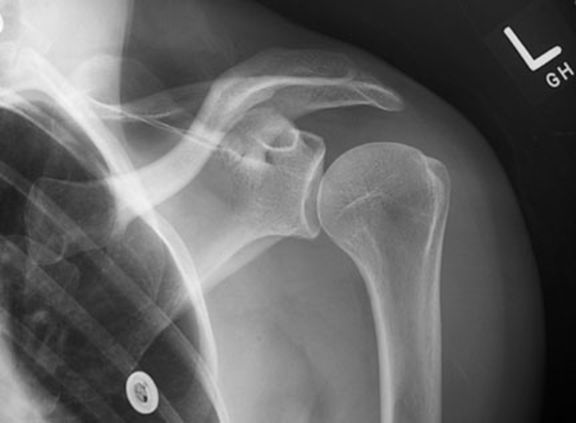

正常肩关节

肩锁关节脱位

前脱位,前内脱位,后脱位。